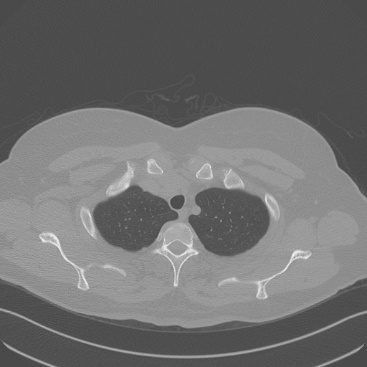

Low-Dose Computed Tomography (LDCT) technique, which reduces the radiation harm to human bodies, is now attracting increasing interest in the medical imaging field. As the image quality is degraded by low dose radiation, LDCT exams require specialized reconstruction methods or denoising algorithms. However, most of the recent effective methods overlook the inner-structure of the original projection data (sinogram) which limits their denoising ability. The inner-structure of the sinogram represents special characteristics of the data in the sinogram domain. By maintaining this structure while denoising, the noise can be obviously restrained. Therefore, we propose an LDCT denoising network namely Sinogram Inner-Structure Transformer (SIST) to reduce the noise by utilizing the inner-structure in the sinogram domain. Specifically, we study the CT imaging mechanism and statistical characteristics of sinogram to design the sinogram inner-structure loss including the global and local inner-structure for restoring high-quality CT images. Besides, we propose a sinogram transformer module to better extract sinogram features. The transformer architecture using a self-attention mechanism can exploit interrelations between projections of different view angles, which achieves an outstanding performance in sinogram denoising. Furthermore, in order to improve the performance in the image domain, we propose the image reconstruction module to complementarily denoise both in the sinogram and image domain.